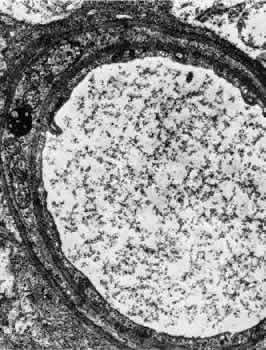

Venules are usually less than 20 μm in diameter.15 The media is composed of a single layer of cells resembling pericytes, containing poorly developed myofilaments and dense bodies. Elastin is not present. The adventitia contains little other than the basement membrane surrounding the pericyte (Fig. 5).

Fig. 5. Electron micrograph of a human retinal venule. E, endothelial cell. The pericyte (P) contains abundant mitochondria and rough-surfaced endoplasmic reticulum. Pinocytotic vesicles are present, and the myofilaments are poorly developed.